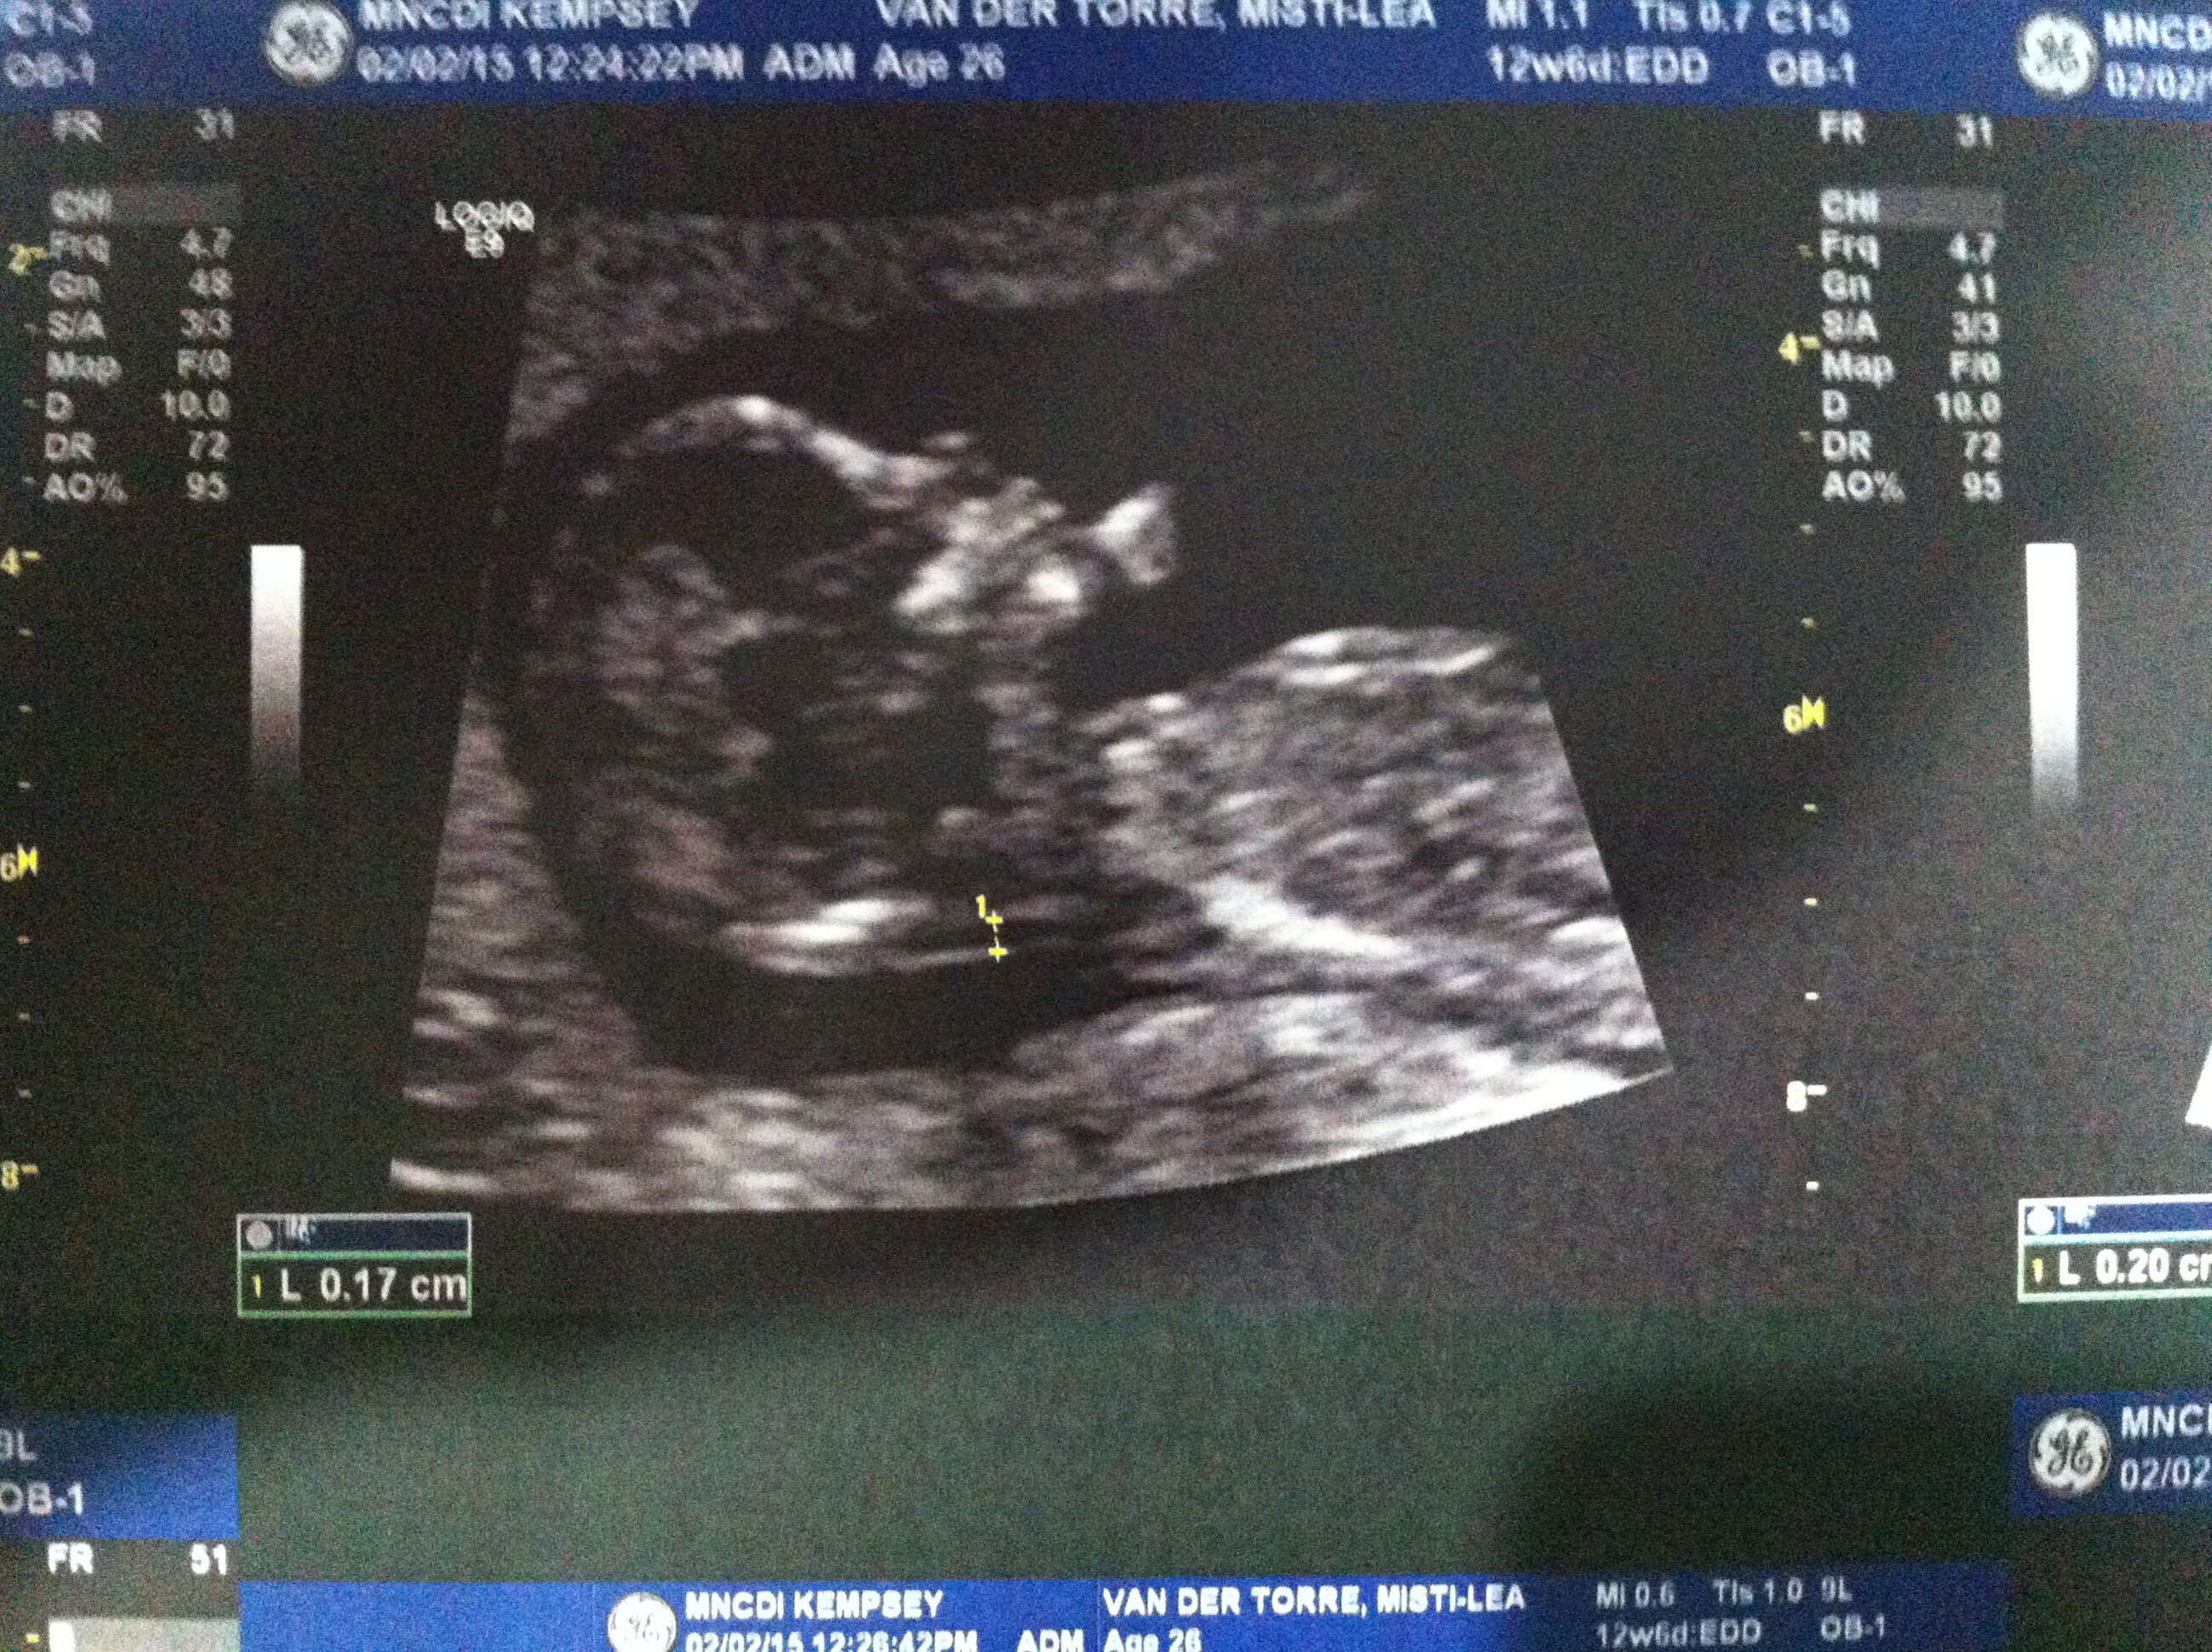

13+1w NT Ultrasound

Hi all! I had my NT sca today and the lady was very unhelpful. When I asked if she knew about the nub theory she went on a big thing about how she didn't believe in it and afterwards whenever she would go anywhere near the nub shot, she would move over or away very quickly so I never got a chance to check it out myself. Quite disappointing but oh well.

I still thought I would give it a go posting here see if anyone can see something I can't otherwise anyone care to guess on skull theory? Attachment 23469Attachment 23470

I can't see any nub. But the skull looks flat at the brow which may indicate boy. Congrats on baby :)

I think I maybe see a very girly nub.

I think I see that girly nub, too

Girl lean based on the newer ones. Cant be 100% though because of the movement. Doesn't believe in nub theory but makes sure to avoid it... Gotta love people like that! Hopefully if you have any more between now and the 20ish week anatomy scan you get someone more helpful!

Slight girl lean but really hard to tell!!

Ditto girly lean more based on seeing pics of other girls at this gestation than guessing off any nub! X

Brow and frontal lobe look boy, nub looks more girly but could be on the rise.

55/45 boy.

I don't see a nub, but boyish skull. GL!